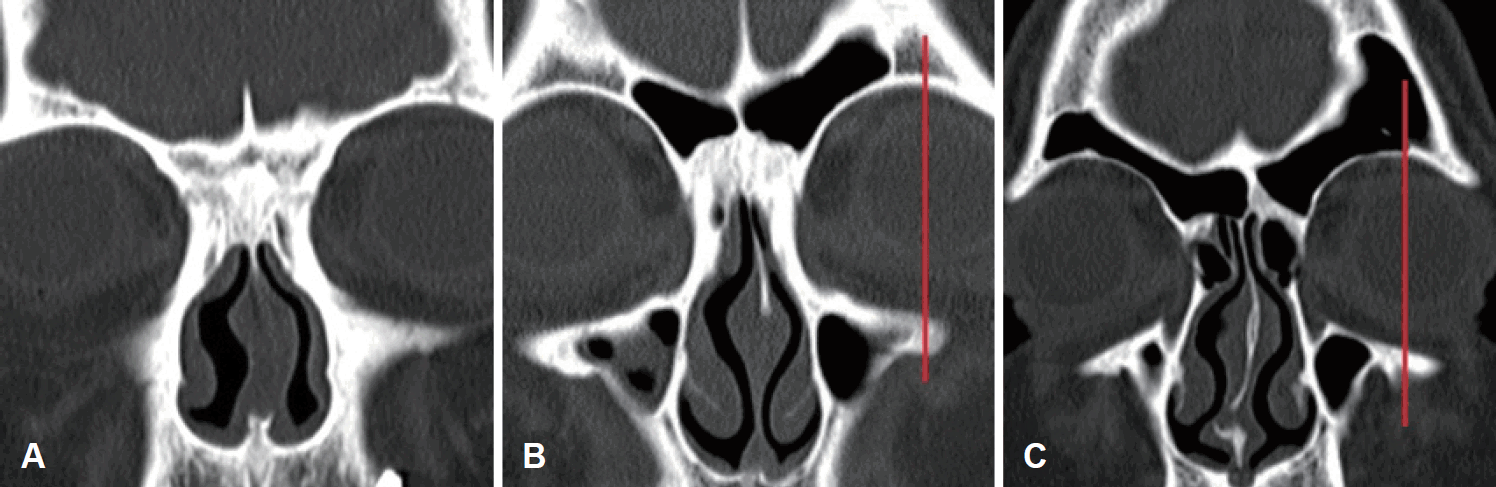

We analyzed 311 PNS CT scans (n=622, including left and right sides). Tomography was performed using Somatom Definition Flash 256-slice CT scanners (Siemens Healthcare, Forchheim, Germany) with axial plane reconstruction of 1 mm slice thickness. We classified FS into type I (aplasia), type II (hypoplasia), and type III (control) (Fig. 1) [1]. In type I, the FS does not pneumatize on the orbital roof at all. Type II shows pneumatization limited to the medial aspect of the midorbital line. FS pneumatization above the orbital roof is defined as type III. Based on the classification by Bolger, et al. [6], the MS was assigned as control and hypoplasia. Type I hypoplasia is characterized by a normal uncinate process, well-defined infundibular passage, and mild sinus hypoplasia. Type II is characterized by absence or hypoplasia of the uncinate process, an ill-defined infundibular passage, and soft-tissue density opacification of a significantly hypoplastic sinus. Type III shows absence of the uncinate process and a profoundly hypoplastic, cleft-like sinus. In our study, we did not come across type III, and thus classified type I and II as hypoplasia of the MS. The SS was classified into sellar and presellar types.

Classification of frontal sinus into the three types on coronal CT. Type I (aplasia) (A), type II (hypoplasia) (B), type III (control) (C). Red line indicates midpupillary line.